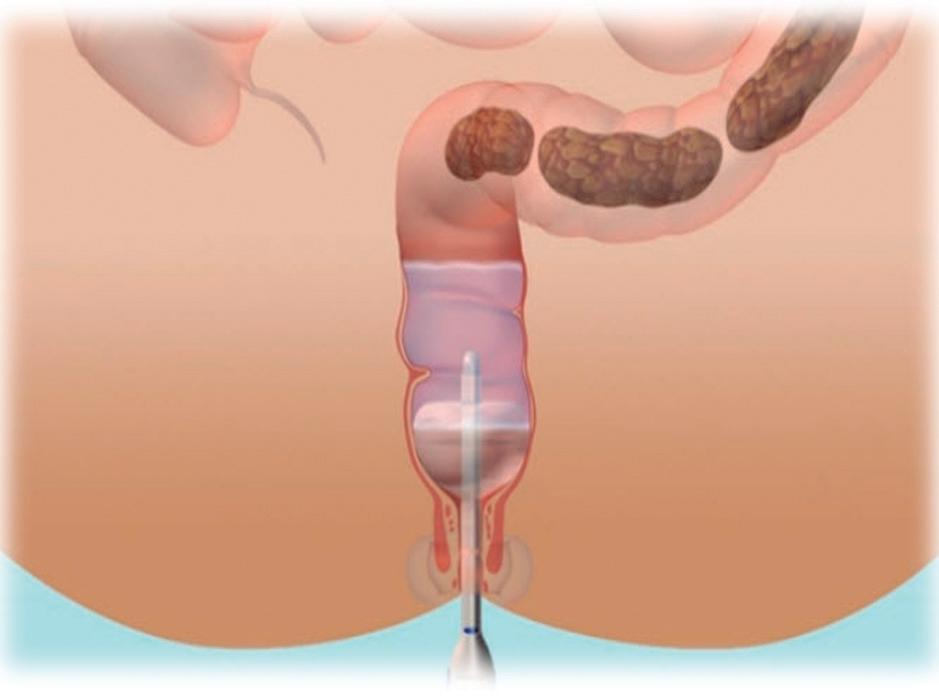

Avances en el tratamiento del estreñimiento refractario pediátrico

Sara Noemí Schaab, María Cielo Gutiérrez